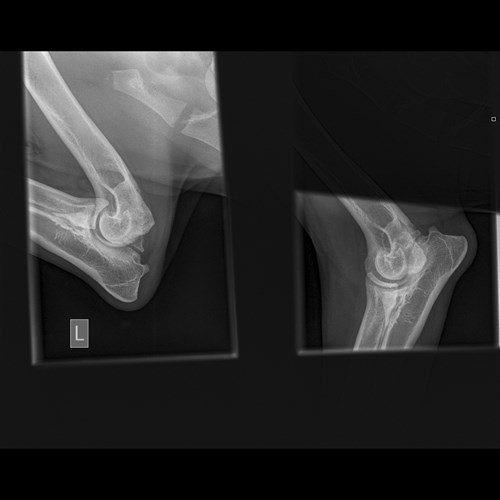

My mom then noticed after a few days she could hear clicking in my elbows every now and again when I moved so decided to take me for some xrays to make sure they were ok.

Sadly the vet gave my mom bad news. I need surgery as soon as possible to remove a piece of loose bone in both my elbows else I am going to become poorly very quickly wihich she does not want me to do.